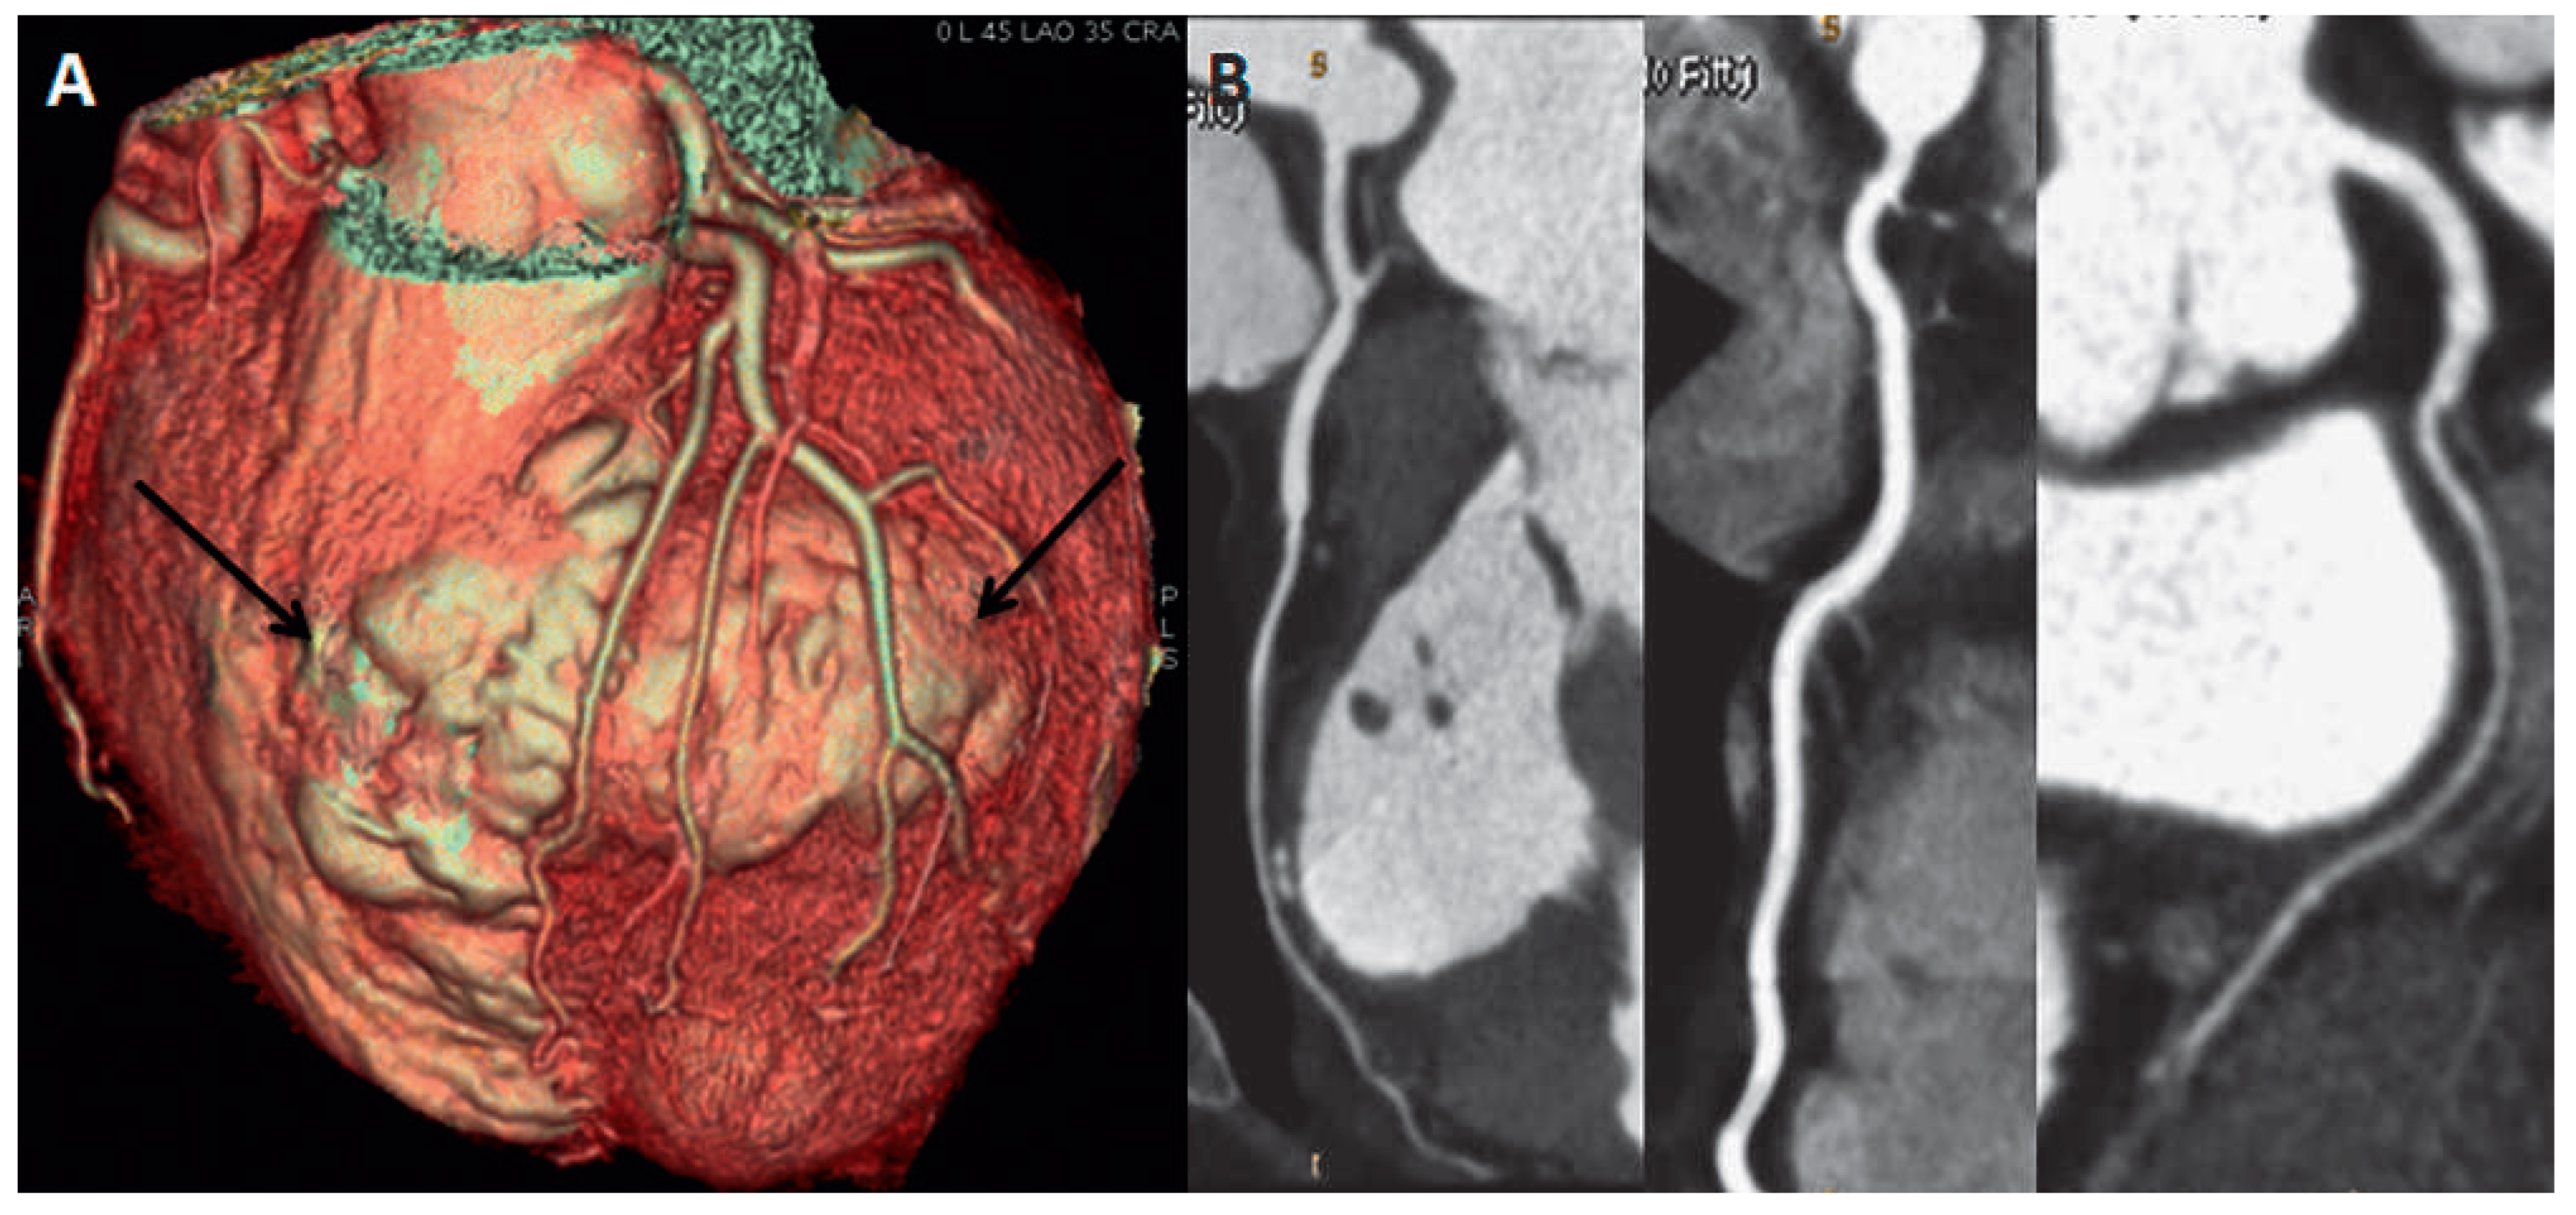

For better understanding of the anatomical relationship of the aneurysm with the coronary tree (planning a surgical resection of the aneurysm), the patient underwent CT angiography. It showed intact left anterior descending artery and diagonal branches without any wall lesions (Figure 3B). The arteries were spreading out extensively over the aneurysm wall. 3D CT volume rendering modality (Figure 3A), however, showed that the aneurysm involved not only the left, but also the right ventricle in its antero-apical region (Figure 3A, arrows). Unfortunately, the previously performed MRI study protocol was dedicated to the LV study so that the involvement of the right ventricle could be neither confirmed nor excluded. We could not repeat the MRI study later on as the patient underwent ICD implantation.

Figure 3. CT angiography shows intact coronary arteries without any wall lesions (B). 3D CT volume rendering modality demonstrates an involvement not only of the left ventricle but also of the right ventricle in its antero-apical region (A, arrows).